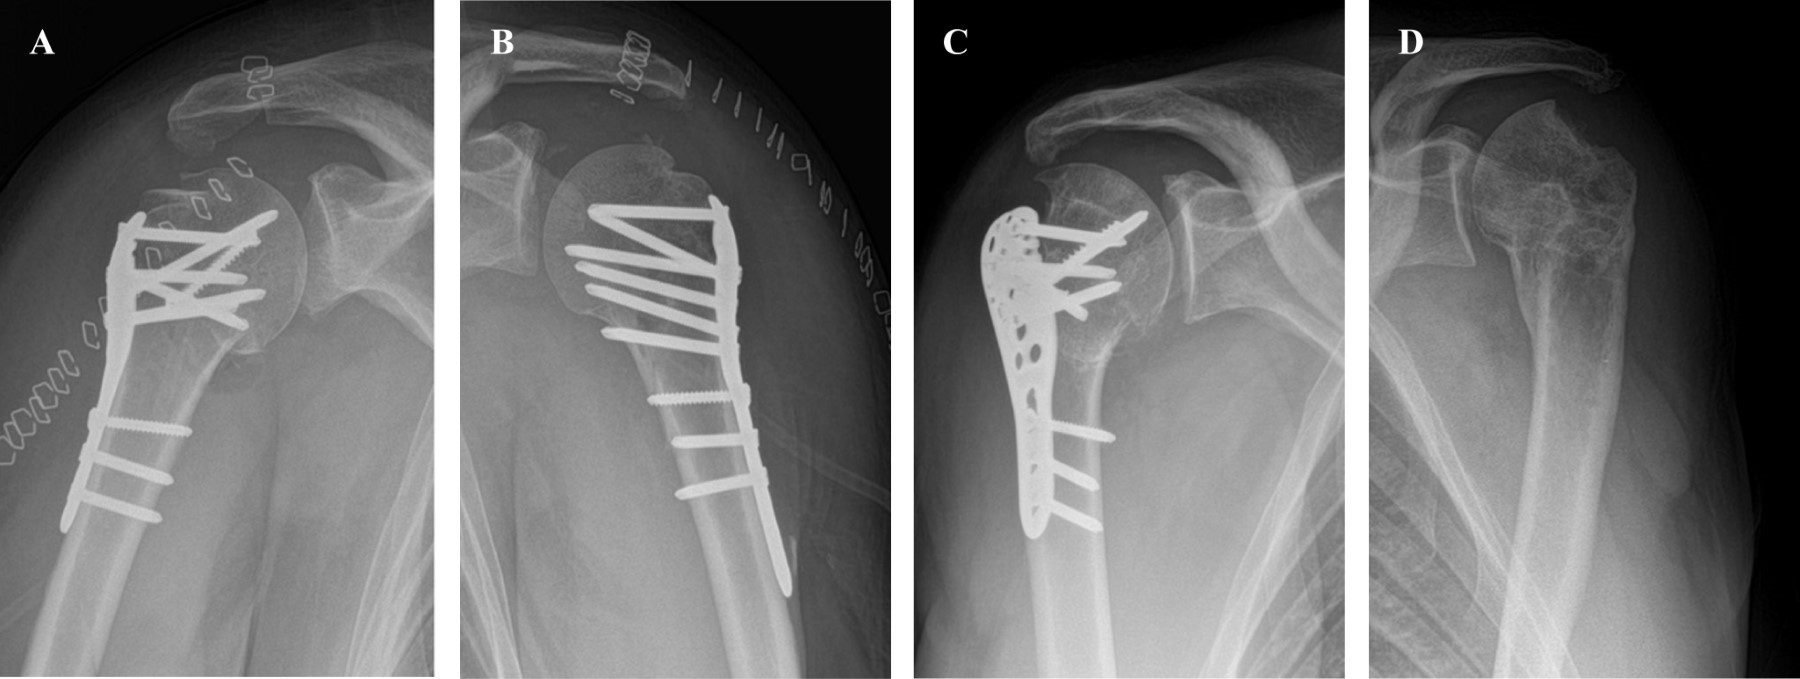

Se decide realizar reducción abierta y osteosíntesis con placa bloqueada bilateral en un tiempo. Se coloca al paciente en posición silla de playa y se preparan los campos quirúrgicos de manera habitual para el hombro derecho. Mediante abordaje deltopectoral clásico se accede al foco de fractura. Con una incisión tipo "mini-open" posterior del tamaño de un portal de artroscopía diagnóstica estándar se realiza una maniobra digital para reducir el fragmento posterior de cabeza humeral. Utilizando suturas de alta resistencia y agujas se logra una reducción provisoria de la fractura. Para fijar ambos fragmentos de la cabeza humeral se usa un tornillo esponjoso rosca parcial 4.0 mm y suturas de alta resistencia. Fijación definitiva de la fractura con placa Philos (Depuy Synthes®) logrando adecuada reducción y estabilidad de fragmentos (Figura 4A). Se aumenta la fijación con suturas de alta resistencia a los tendones del manguito rotador que se anudan a la placa. Cierre por planos del hombro derecho, curación e inmovilización de la extremidad con inmovilizador universal de hombro.

Inmediatamente a continuación se prepara el campo quirúrgico del hombro izquierdo. Se realiza de nuevo abordaje deltopectoral clásico para llegar al foco de fractura utilizando un portal posterior accesorio para manipulación digital y reducción de la cabeza humeral. Se realiza fijación y osteosíntesis de la misma manera que la descrita para el hombro derecho a excepción del tornillo de esponjosa, ya que el fragmento anterior pudo fijarse adecuadamente sólo con el uso de suturas de alta resistencia (Figura 4B).

El manejo postoperatorio consistió en el uso de inmovilizador de hombro bilateral por cuatro semanas. Se entregó una pauta de ejercicios pendulares de flexoextensión de codo y ejercicios de puño a realizar desde la segunda semana postoperatoria a tolerancia (según el nivel de dolor). En el control radiográfico del primer mes se constata pérdida de reducción de la tuberosidad mayor izquierda. Se decide realizar cirugía de revisión logrando fijación adecuada del fragmento con suturas de alta resistencia.

Se da seguimiento a un año desde la cirugía inicial y se constata que el paciente ha recuperado fuerza y movilidad en el hombro derecho. El hombro izquierdo aún presenta severa limitación del rango articular sobre todo en rotación externa. Se decide en este punto realizar una cirugía de liberación articular artroscópica y retiro de osteosíntesis del hombro izquierdo.

En su último control a dos años desde el trauma (Figura 4C y D) el paciente muestra evolución favorable, concordante con escalas funcionales evaluadas (Tabla 1). En la Figura 5 se observa el rango de movimiento clínico del paciente a los dos años de seguimiento desde la lesión inicial.